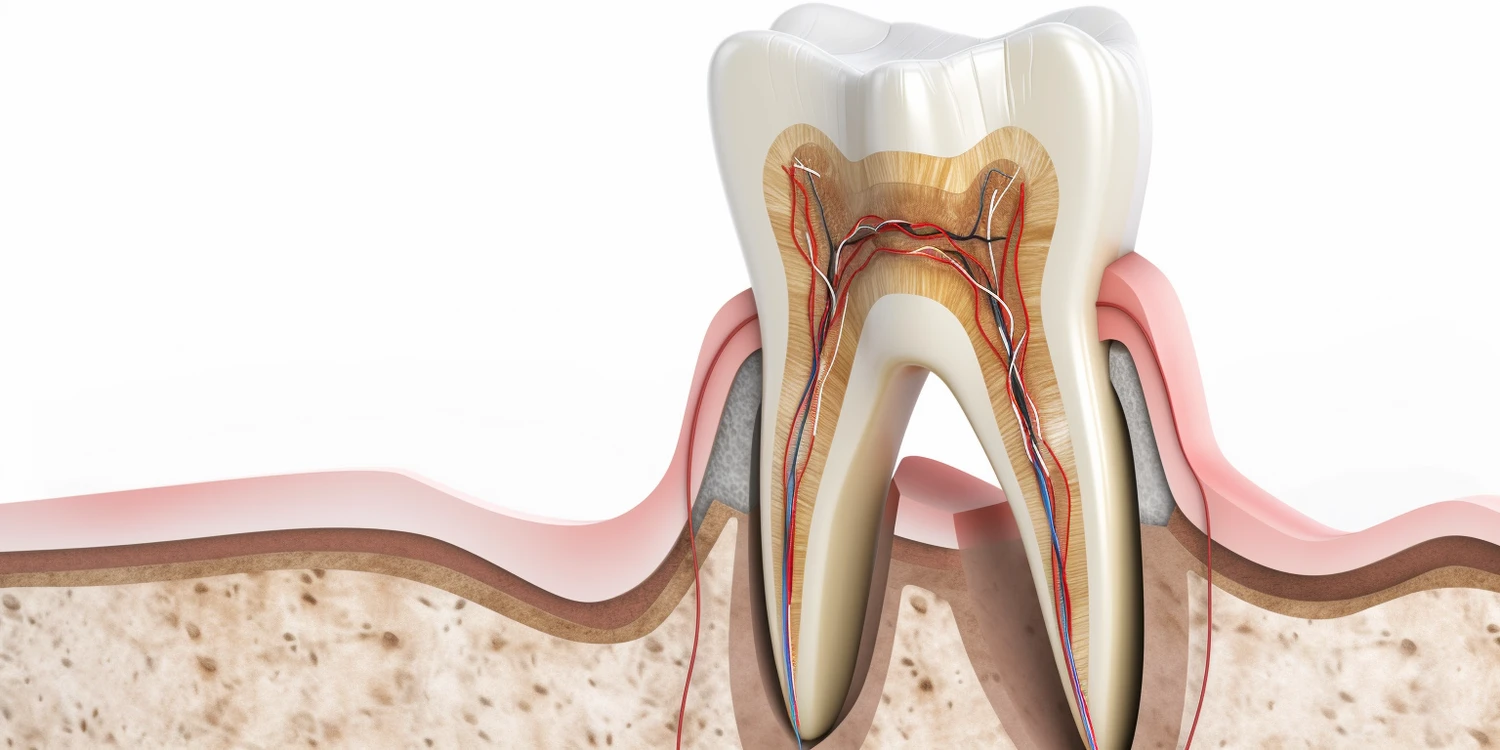

Choć dentyści są uznawani za lekarzy, istnieją istotne różnice między stomatologią a innymi dziedzinami medycyny. Stomatologia koncentruje się głównie na zdrowiu jamy ustnej oraz leczeniu problemów związanych z zębami i dziąsłami. W przeciwieństwie do lekarzy ogólnych czy specjalistów medycznych zajmujących się innymi obszarami ciała, dentyści mają bardziej wyspecjalizowaną wiedzę i umiejętności dotyczące konkretnego obszaru anatomicznego. Dodatkowo stomatologia obejmuje różnorodne procedury, takie jak ekstrakcje zębów, leczenie kanałowe czy ortodoncja, które wymagają precyzji i doświadczenia. Różnice te wpływają również na sposób kształcenia przyszłych specjalistów – podczas gdy lekarze ogólni uczą się o całym ciele ludzkim i różnych chorobach, dentyści skupiają się głównie na zagadnieniach związanych ze zdrowiem jamy ustnej.

W dziedzinie stomatologii istnieje wiele specjalizacji, które pokazują różnorodność tego zawodu oraz jego złożoność. Dentyści mogą wybierać spośród różnych ścieżek kariery, co pozwala im skupić się na konkretnych aspektach zdrowia jamy ustnej. Jedną z najpopularniejszych specjalizacji jest ortodoncja, która zajmuje się diagnozowaniem i leczeniem wad zgryzu oraz nieprawidłowości w układzie zębów. Ortodonci stosują aparaty ortodontyczne, aby poprawić estetykę uśmiechu oraz funkcjonalność zgryzu. Inną ważną specjalizacją jest stomatologia dziecięca, która koncentruje się na opiece nad najmłodszymi pacjentami. Dentyści dziecięcy mają za zadanie nie tylko leczyć, ale także edukować dzieci i ich rodziców w zakresie higieny jamy ustnej. Kolejną istotną dziedziną jest chirurgia stomatologiczna, która obejmuje bardziej inwazyjne procedury, takie jak ekstrakcje zębów mądrości czy operacje implantologiczne. Warto również wspomnieć o periodontologii, która zajmuje się chorobami dziąseł i tkanek otaczających zęby.